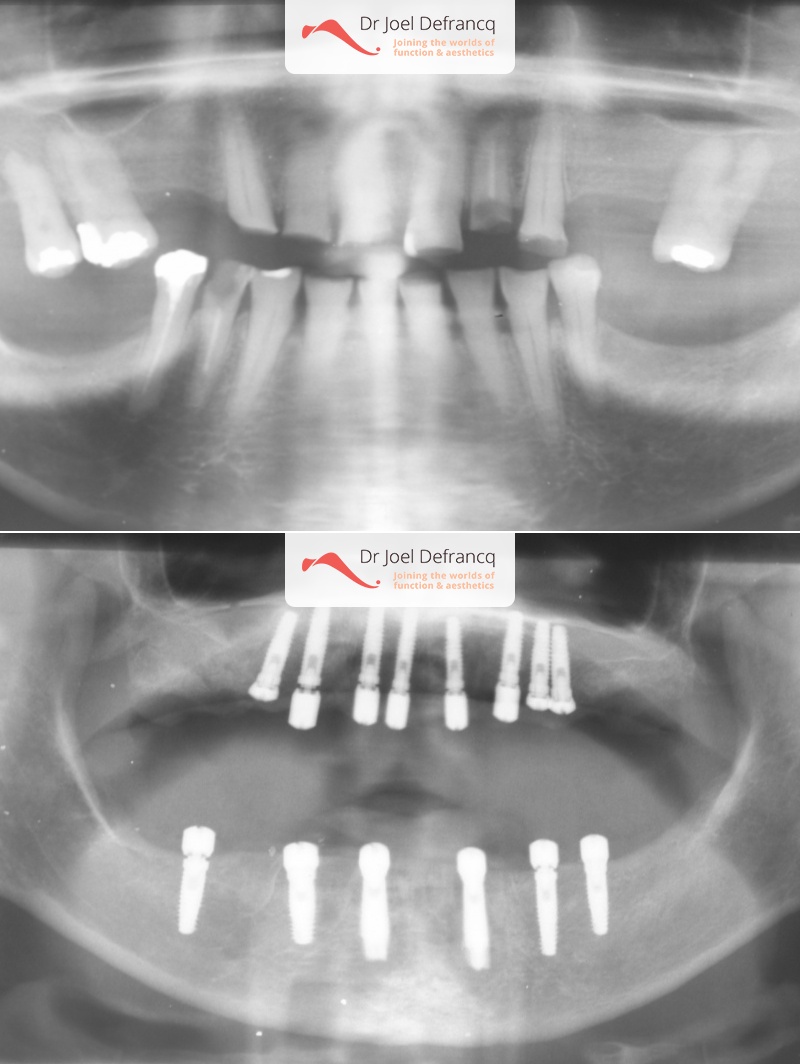

Bieke

Dentale diagnose

- Klasse I

Behandeling tandheelkundige implantaten

- Vaste tanden op implantaten (bovenkaak)